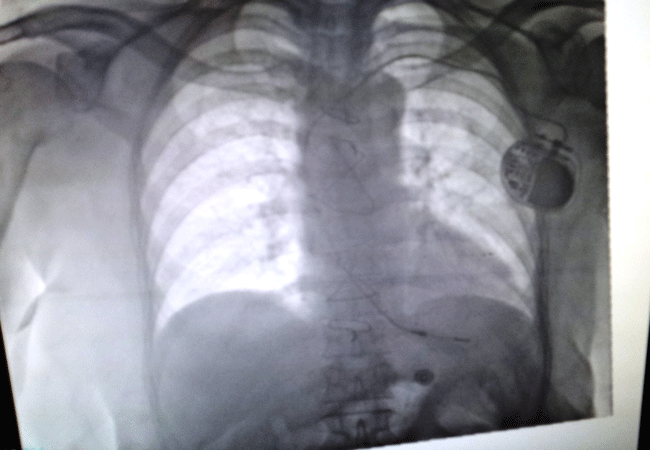

Iğdır Devlet Hastanesi'nde görev yapan uzman Dr. Abdullah Çirit tarafından, kalp krizi geçiren yaşlı bir hastaya 'kalcı kalp pili' takıldı.

Iğdır Devlet Hastanesi’nde görev yapan kardiyoloji uzmanı Dr. Abdullah Çirit, kalp krizi geçirmesi sonucu kendilerine gelen yaşlı hastaya ilk önce kalp pilini taktıklarını, daha sonra da Iğdır’da bir ilki gerçekleştirerek kalıcı kalp pilini taktıklarını söyledi.